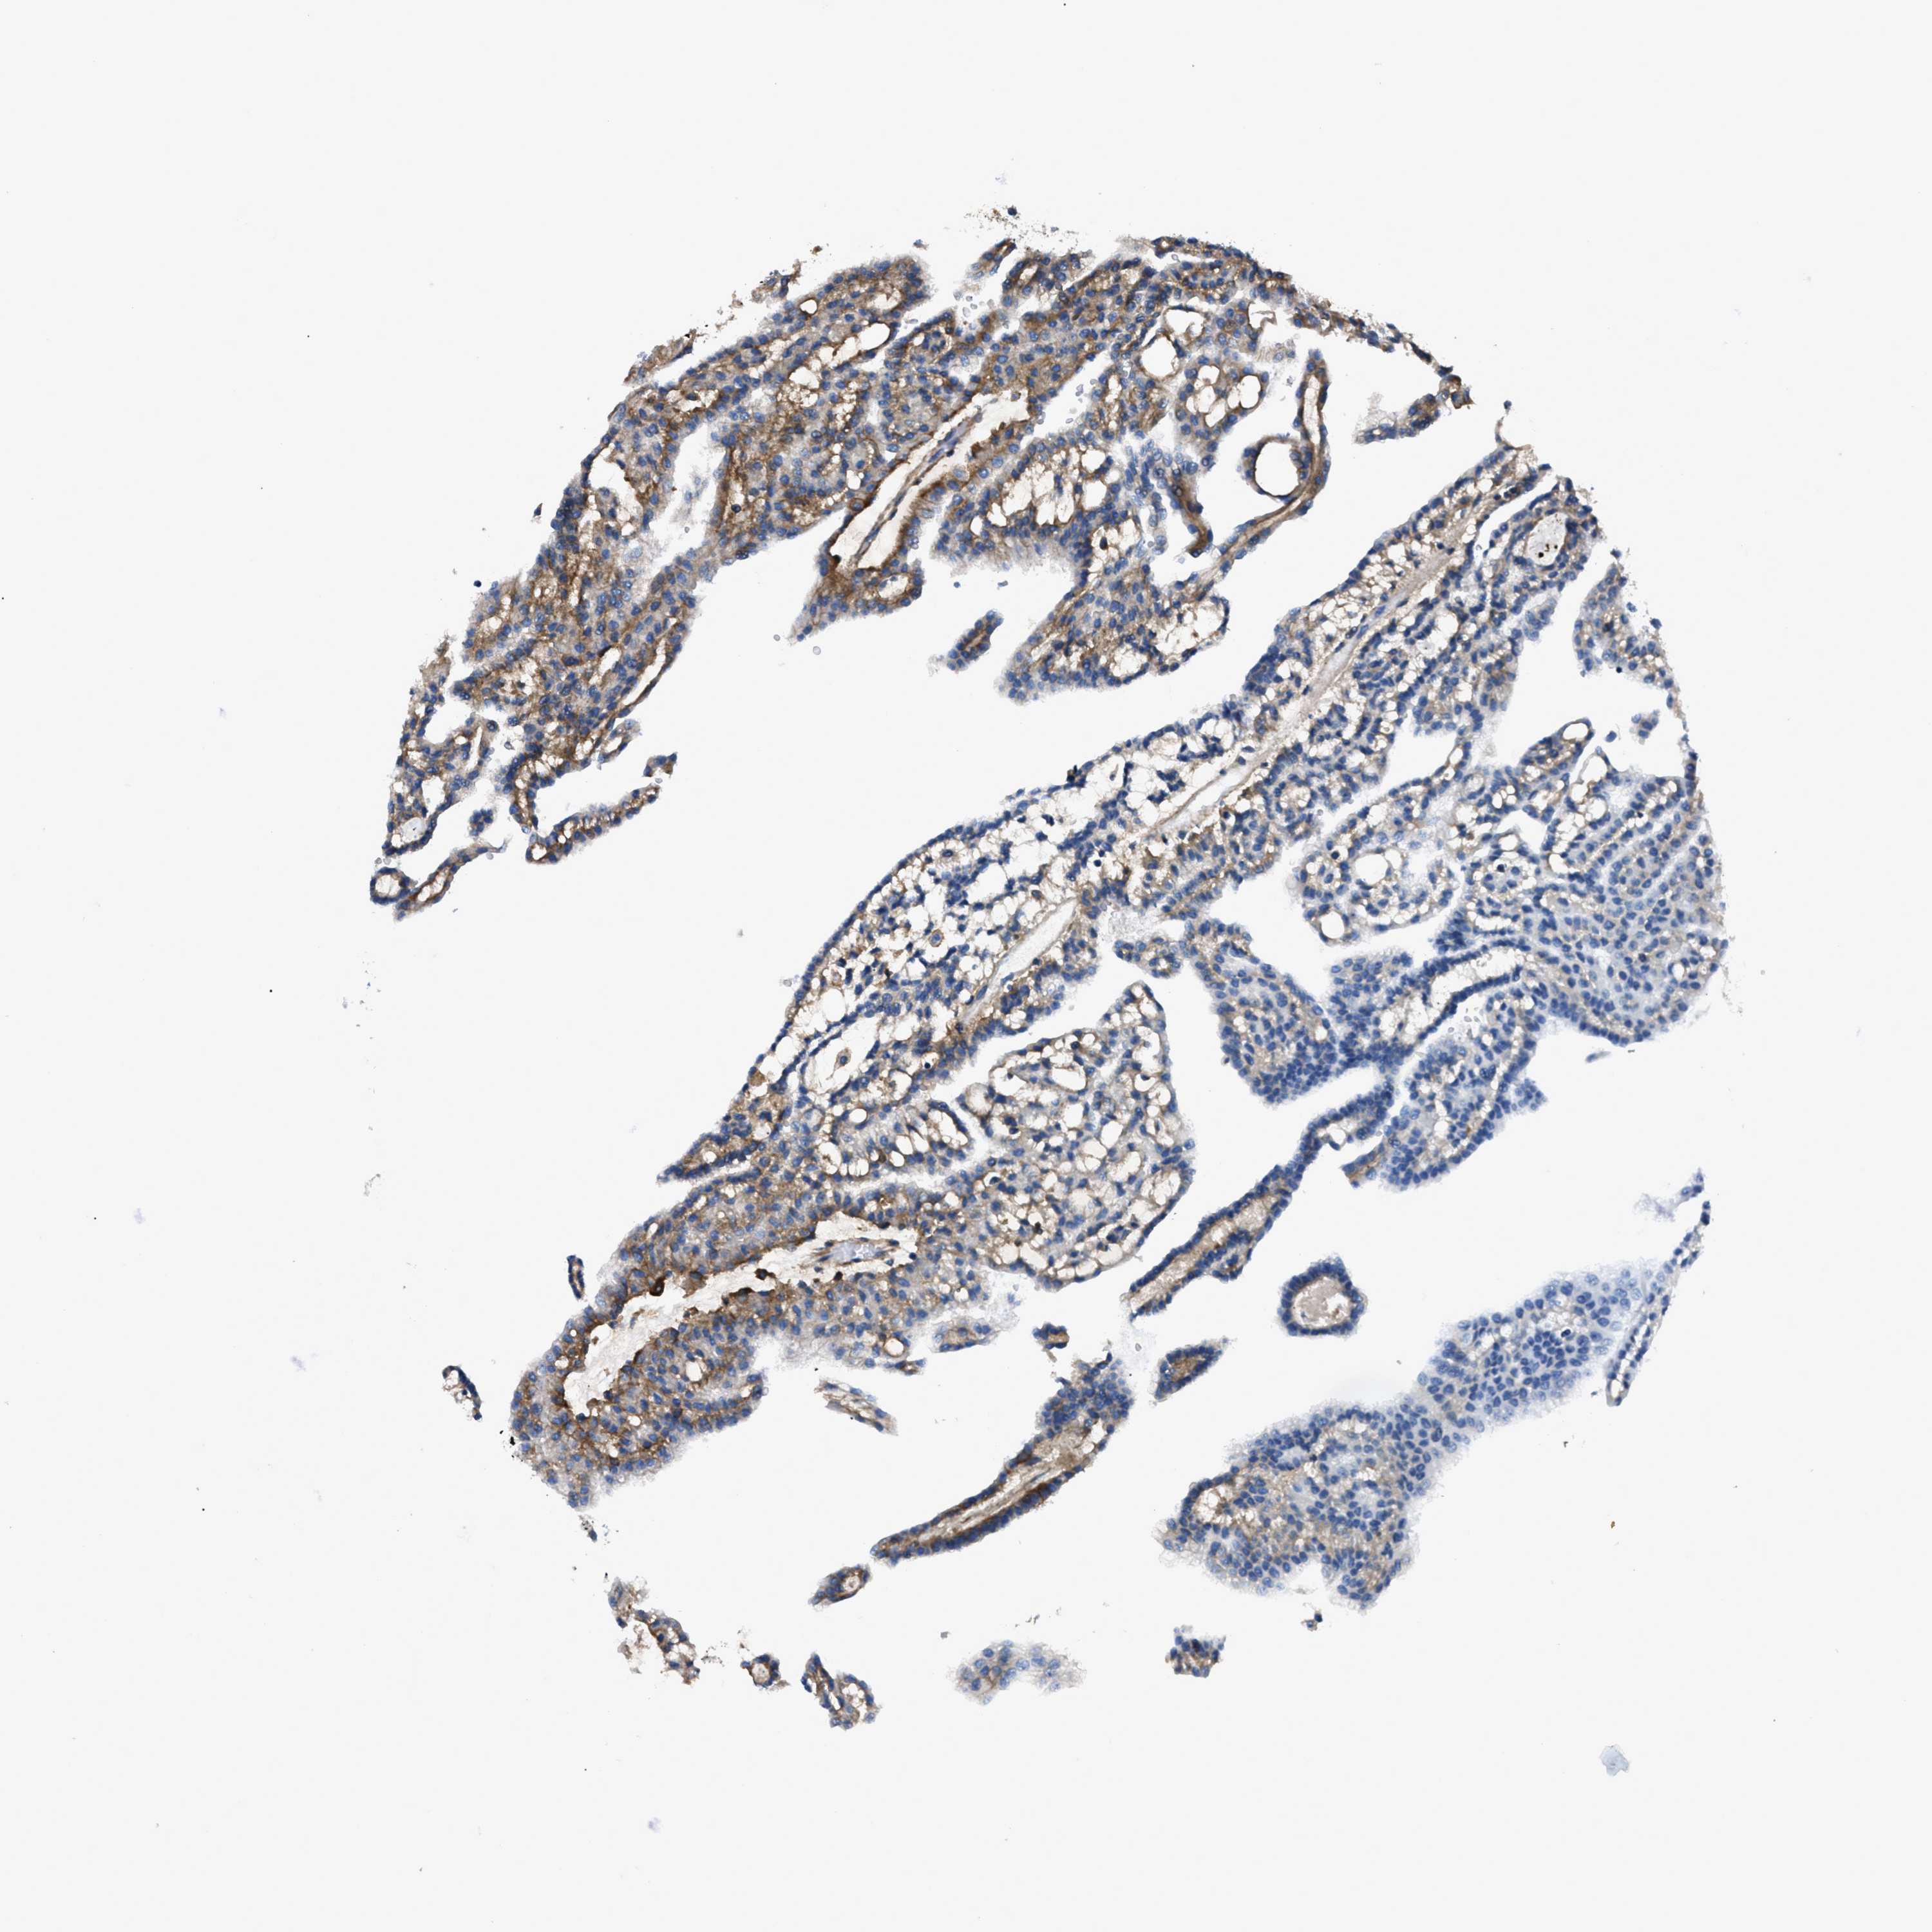

KIDNEY RENAL PAPILLARY CELL CARCINOMA (TCGA) - Interactive survival scatter ploti

The Survival Scatter plot shows the clinical status (i.e. dead or alive) for all individuals in the patient cohort, based on the same data that underlies the corresponding Kaplan-Meier plots. Patients that are alive at last time for follow-up are shown in blue and patients who have died during the study are shown in red.

The x-axis shows the expression levels (FPKM) of the investigated gene in the tumor tissue at the time of diagnosis. The y-axis shows the follow-up time after diagnosis (years). Both axes are complimented with kernel density curves demonstrating the data density over the axes. The top density plot shows the expression levels (FPKM) distribution among dead (red) and alive patients (blue). The right density plot shows the data density of the survived years of dead patients with high and low expression levels respectively, stratified using the cutoff indicated by the vertical dashed line through the Survival Scatter plot. This cutoff is automatically defined based on the FPKM cutoff that minimizes the p-score. The cutoff can be changed by dragging the vertical line or by entering a cutoff value in the square labeled "Current cut-off".

Under the Survival Scatter plot the p-score landscape (black curve; left axis) is shown together with dead median separation (red curve; right axis). Dead median separation is the difference in median mRNA expression between patients who have died with high and low expression, respectively. It is calculated as follows: median FPKM expression of dead patients with high expression - median FPKM expression of dead patients with low expression. This is intended to aid the user in visually exploring custom cutoffs and the associated p-scores and dead median separation.

Individual patient data is displayed and can be filtered by clicking on one or more of the category buttons on the top of the page. Categories describing expression level and patient information include: high, low, alive, dead, female, male and tumor stages. The scale of the x-axis can be toggled between linear and log-scale by clicking on the "x log" button. Mouse-over function shows TCGA ID, patient information and mRNA expression (FPKM) for each patient.

& Survival analysisi

Kaplan-Meier plots summarize results from analysis of correlation between mRNA expression level and patient survival. Patients were divided based on level of expression into one of the two groups "low" (under cut off) or "high" (over cut off). X-axis shows time for survival (years) and y-axis shows the probability of survival, where 1.0 corresponds to 100 percent.

CD276 is not prognostic in Kidney Renal Papillary Cell Carcinoma (TCGA)